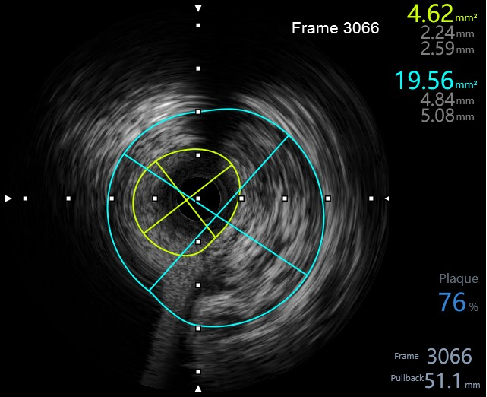

2,由远至近IVUS评估,不同切面对应不同面积,提示左主干面积4~5mm²,属于重度狭窄,需要介入治疗。

3,担心guiding深插对开口2次损伤,放窦外导丝进一步保护,根据ivus指导,植入4.0x18mm 支架。

5,植入后,复查ivus,评估支架植入效果。

6,IVUS 评估后,最小面积未达到8mm²最小官腔面积。需进一步后处理。

7,给与4.0x15mm非顺应性球囊进行高压后扩张,压力维持在16~20atm。最后检查血管影像。